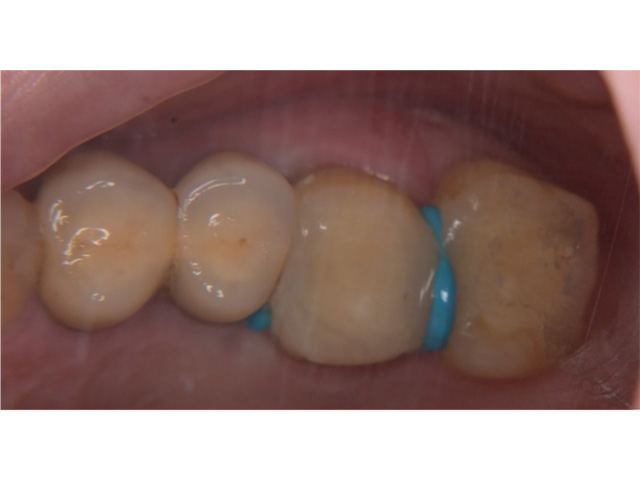

術前(主訴は左上の奥歯の歯ぐきの腫れが気になるということでした)

左上の第一大臼歯および第二大臼歯をラバーダムというゴムのマスクを使用して無菌的な環境の中で歯の神経の治療を行いました。

根管治療終了後のレントゲン写真です。

根の先までお薬を詰めることができましたが1か月後歯ぐきの腫れが再発したため患者さまとご相談し意図的再植術を行い感染源の除去を行うことしました。

① 隣の歯に負担をかけないように事前に水色のゴムを入れて歯と歯の間を開きます

② 一度原因歯を抜去します

③ 抜いた歯を口腔外で視診し根が折れていないか確認します。

そのあと歯根の先の部分を口腔外で3ミリ程度切断し、裏側からMTAセメントというセメントを詰めて口腔内に戻し、縫合した後レントゲン写真を撮影します。

現在歯ぐきの腫れも、歯の痛みもなく経過良好です。

手前の歯については患者さまのご希望により経過観察中です。

| 主訴 | 左上の奥歯の歯ぐきが腫れて違和感が続いている |

|---|---|

| 治療内容 | 左上第一大臼歯および第二大臼歯の根管治療(ラバーダム防湿下)及び左上第一大臼歯の意図的再植術 |

| 治療回数・期間 | 6回 内訳【根管治療:3回(2歯合わせて)、意図的再植術:1回、被せものの作成:2回】 |

| 費用 | 保険適応 |

| リスク・副作用 | 根管治療は術前の精密な診査診断およびラバーダム防湿を用いた無菌環境下での治療によって成功率は高まってきましたが治療の成否を決める多くの要素があるため、根管治療がなされた後も再治療や外科処置、抜歯となる可能性が少なからずあります。また治療中には器具の破折や穿孔、修復物の損傷、歯の破折、術中・術後の痛みや腫れが生じることが稀にあります。根尖病変(再感染)を防ぐには適合の良好な補綴物を作製することや定期的なかみ合わせのチェックが必要です。 |